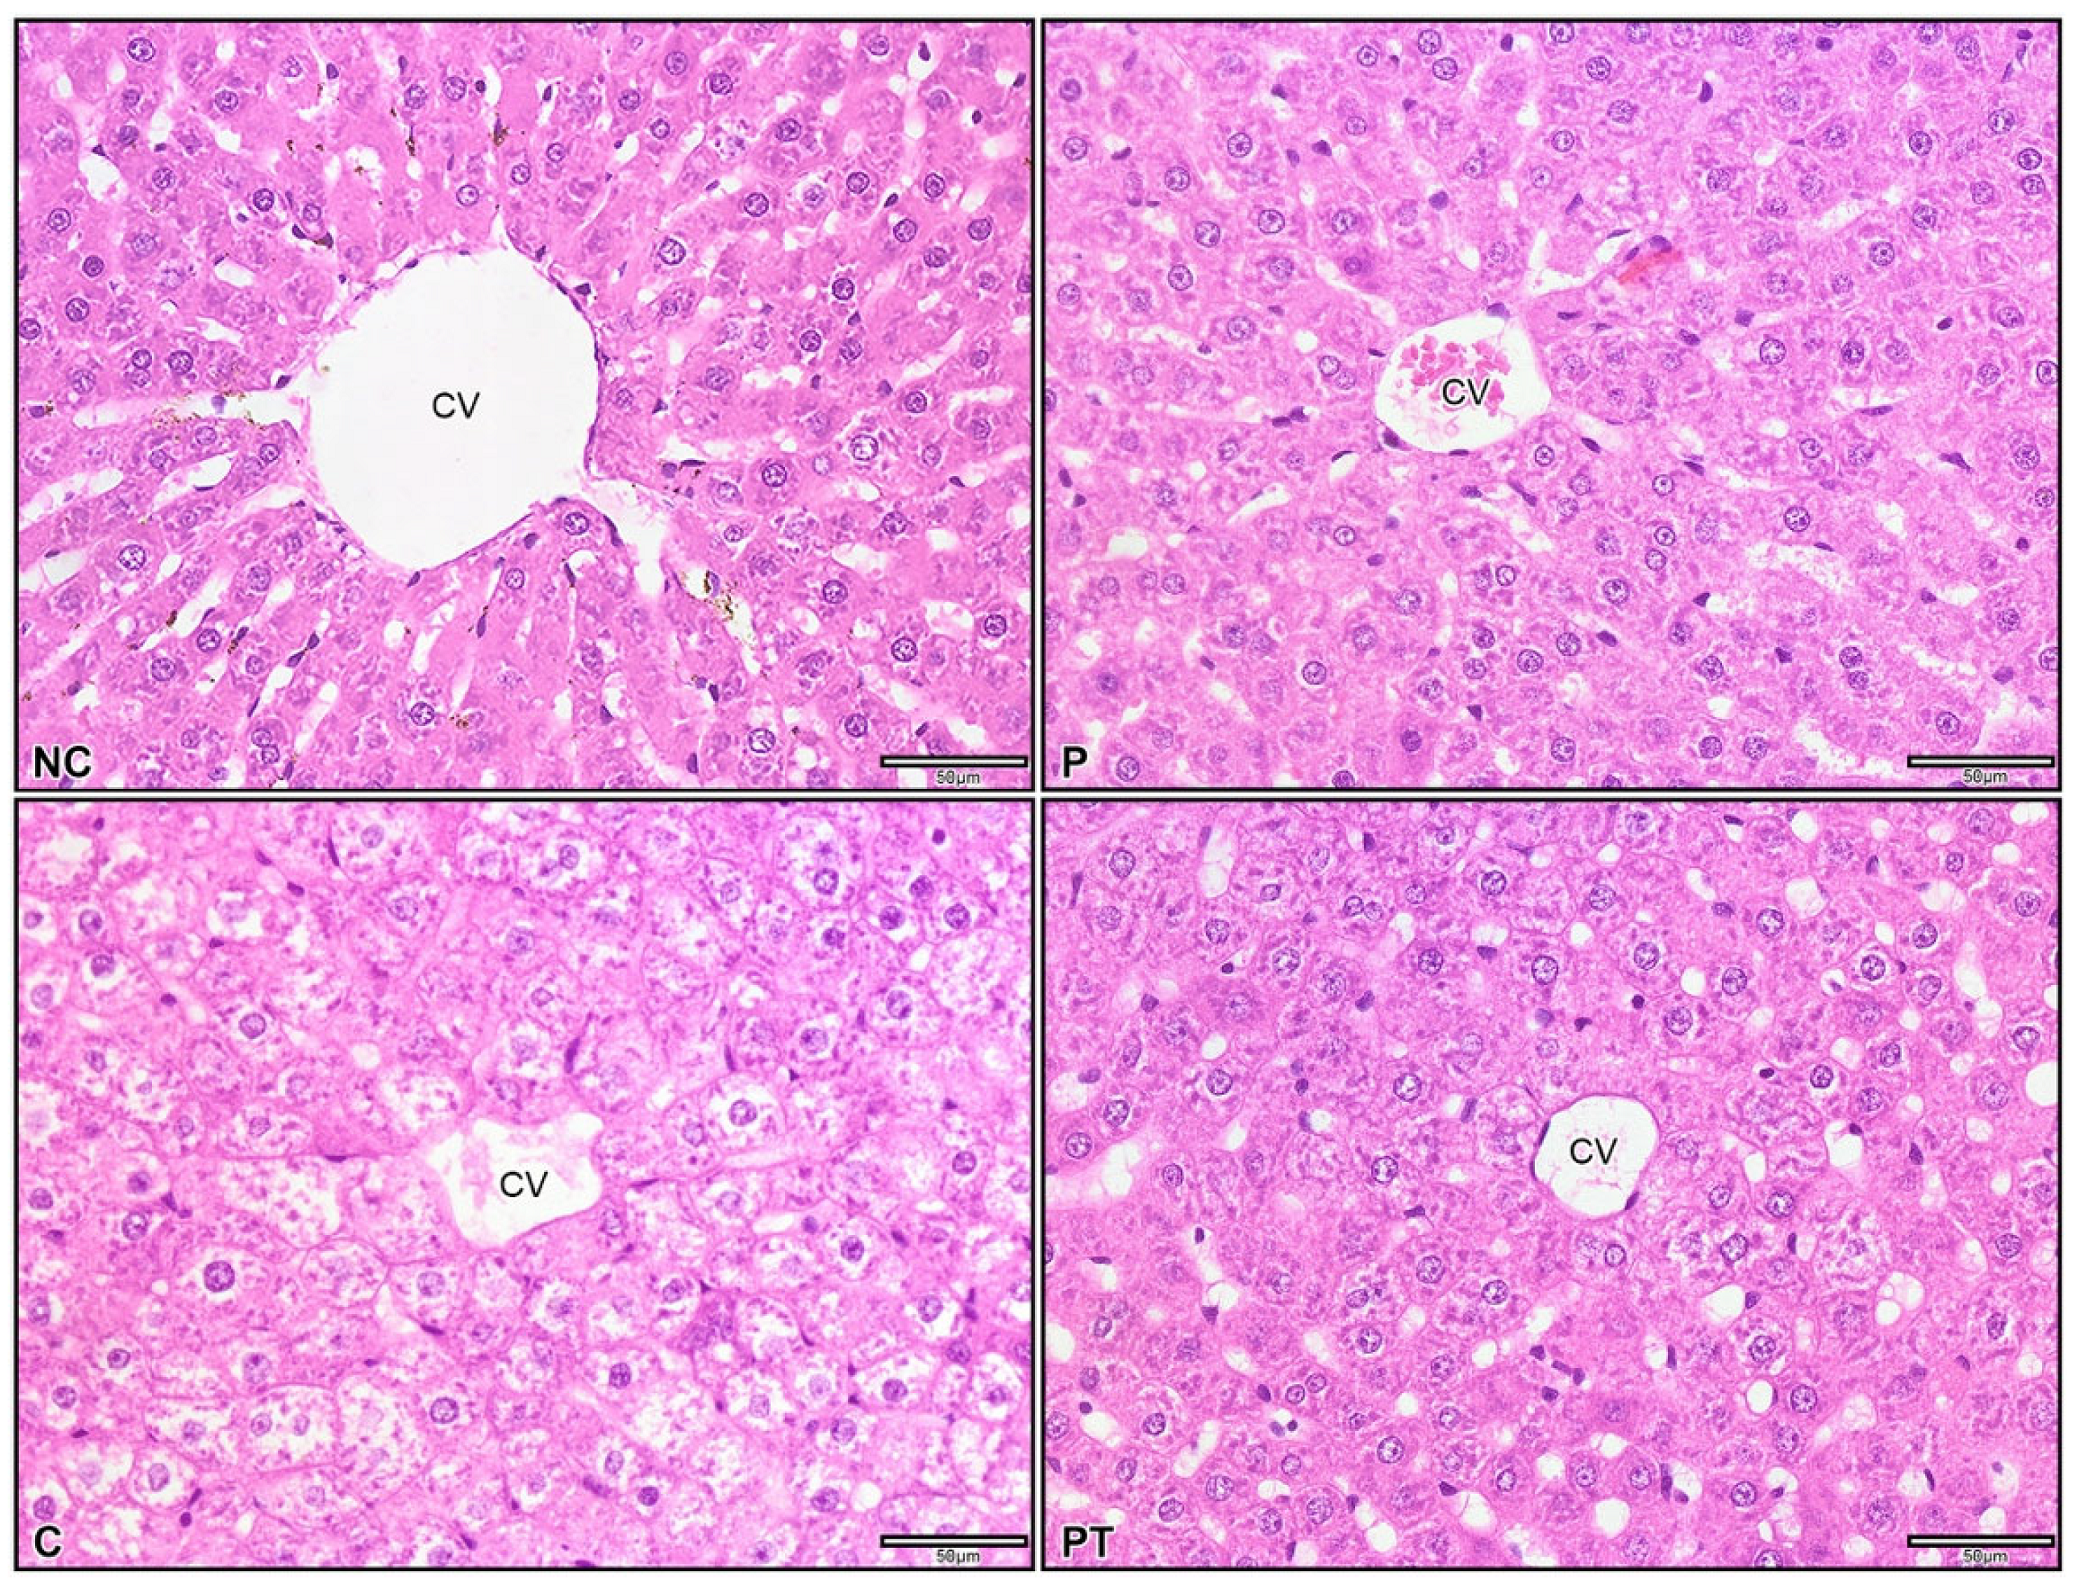

3.5. Effect of Probiotic L. paracasei Strain MSMC39-1 on Colon and Liver Tissue Histology in DSS-Induced Colitis Rats